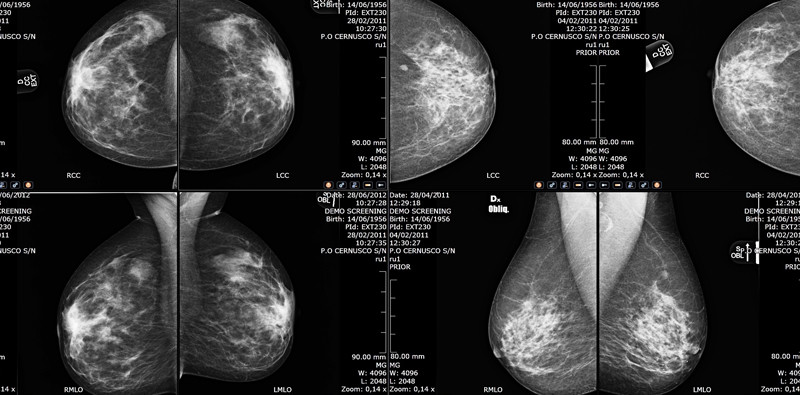

SUITESTENSA MG cuenta con herramientas avanzadas para la gestión y el post-procesamiento de las imágenes y los datos mamográficos, con particular atención a la comparación ergonómica, funcional y automatizada de los estudios anteriores.

Examen comparativo automático del estudio actual y anterior con espacio de trabajo especializado para ambos, incluso en los casos en que los estudios pertenezcan a diferentes series o pacientes.